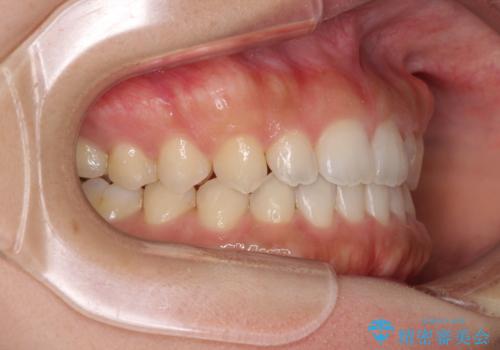

気になる隙間の再矯正 前歯をインビザライン・ライトで改善

- 後戻りによる上下前歯の隙間を気にして来院された患者様です。

歯列不正はそれほど大きくなかったため、インビザライン・ライトを用いて矯正治療を行うこととしました。

無理のないペースで治療を進め、9ヶ月で終えることができました。